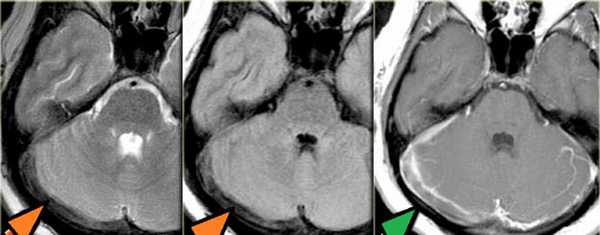

Тромбоз правого поперечного синуса - гипоинтенсивные участки по Т2 (внутриклеточный дезоксигемоглобин).

Для подтверждения тромбоза венозного синуса и определения точной локализации и протяженности тромба необходимо проведение МР-венографии.

МР-венография - отсутствие визуализации кровотока в правом поперечном синусе и яремной вене.

МРТ головного мозга: справа (зеленая стрелка) на Т2-взвешенном изображении отмечается имеющийся в норме феномен «пустоты потока» от правого сигмовидного синуса и яремной Вены. Слева (оранжевая стрелка) отмечается аномально высокий сигнал, в результате, вероятнее, тромбоза. Для подтверждения синус-тромбоза и окончательного определения локализации и протяженности тромбоза необходимо проведение МР-венографии.

МР-венография: тромбоз левого поперечного синуса. Отмечается потеря МР-сигнала от левого поперечного синуса.

Наличие визуализации синуса на «сырых» данных или же МРТ головного мозга подтверждает тромбоз синуса и исключает его гипоплазию.

МР-венография: тромбоз правого поперечного синуса. Отмечается потеря МР-сигнала от правого поперечного синуса.

Наличие визуализации синуса на «сырых» данных или же МРТ головного мозга подтверждает тромбоз синуса и исключает его гипо- и аплазию.

Тромбоз правого поперечного синуса. Отсутствие феномена «пустоты потока» от правого поперечного синуса на МРТ головного мозга. Отсутствие визуализации правого поперечного синуса на МР-венографии.